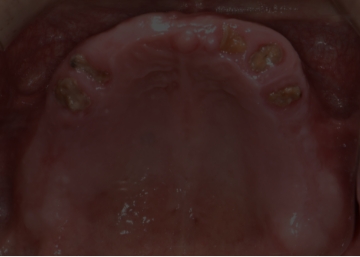

임플란트 : 손 ** 님 (50대)

Before Before

2020.02.30

After After

※ 더서울치과의원은 의료법을 준수하며 위 케이스는 실제 환자의 동의를 얻은 사례로 치료 전, 후가 동일한 환경에서 촬영되었습니다.

환자 케이스에 따라 부작용이 발생할 수 있습니다. 이 부분은 의료진의 충분한 상담과 체크를 통해 예방하고 줄일 수 있습니다.

[임플란트 부작용] 수술 후 관리가 소홀할 경우 출혈, 주위염 등의 부작용이 발생할 수 있어 구강 위생을 철저히 유지하고, 정기적인 검진을 통해 상태를 점검하는 것이 중요합니다.

환자 특징

환자 특징01무치악 상태

환자 특징02수년간 무치악으로 지내심

임플란트가 불가능할것이라

생각하고 내원

위, 아래 6개씩 식립

디지털 풀아치 임플란트